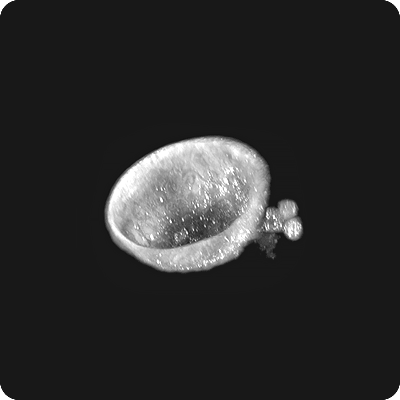

- 3D 생물학 (오가노이드/스페로이드): 오가노이드, 스페로이드, 미세 유체 장치 등 복잡한 3D 배양 세포 및 조직을 이해하는 데 필수적이며, 살아있는 3D 샘플의 비표지, 고해상도, 실시간 시각화 및 장기 종단 연구를 가능하게 합니다.

토모큐브는 홀로토모그래피와 관련된 모든 이론, 광학, 하드웨어, 소프트웨어, AI 기술들을 자체적으로 개발하고 있으며 이를 통해 글로벌 시장에서 초격차를 유지하고 있습니다. 박용근 토모큐브 대표이사는 "토모큐브는 홀로토모그래피 기술로 세계에서 가장 앞서 있으며 경쟁사 대비 5년 이상의 기술 초격차를 유지 중"이라며 "오가노이드와 같은 3차원 샘플을 찍을 수 있는 기술력을 보유한 회사는 토모큐브가 유일하다"고 설명합니다. 경쟁사의 나노라이브 현미경은 내부가 복잡하고 측정 단계가 여러 단계로 직관적이지 않으며, 특히 두꺼운 오가노이드 촬영이 어렵다는 단점이 있습니다. 반면 토모큐브의 2세대 기술은 LED 광원을 사용하여 세포의 절단 없이 두꺼운 오가노이드를 실시간으로 관찰 할 수 있습니다. 제품의 수익률이 50%에 육박한다는 것은 시장의 독점적인 공급자를 나타내는 중요한 지표입입니다. 토모큐브는 또 하나의 패러다임을 창조한 시장의 지배자이자 파괴자입니다.